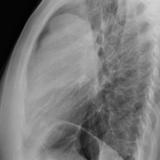

Thymic carcinoma Lat

Date: 08/15/2012

Views: 10103